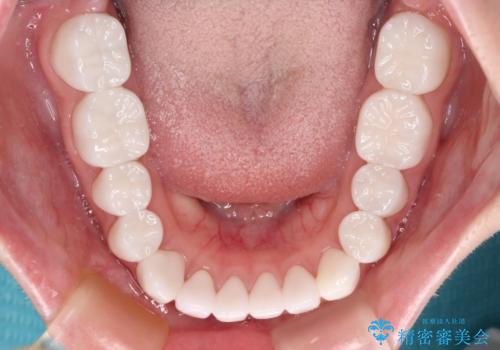

より白さが目立つように、自然な仕上がりではなく、作り物の雰囲気があるフルジルコニアクラウンにて補綴治療を行いました。